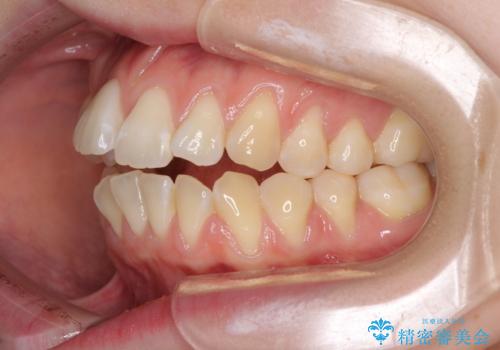

気になるデコボコとオープンバイト インビザラインでの矯正治療

- 前歯のデコボコと上下が開いていることを気にして来院された患者様です。

いわゆるオープンバイトは、インビザラインによる治療が適しているため、インビザラインにて治療を行うこととしました。